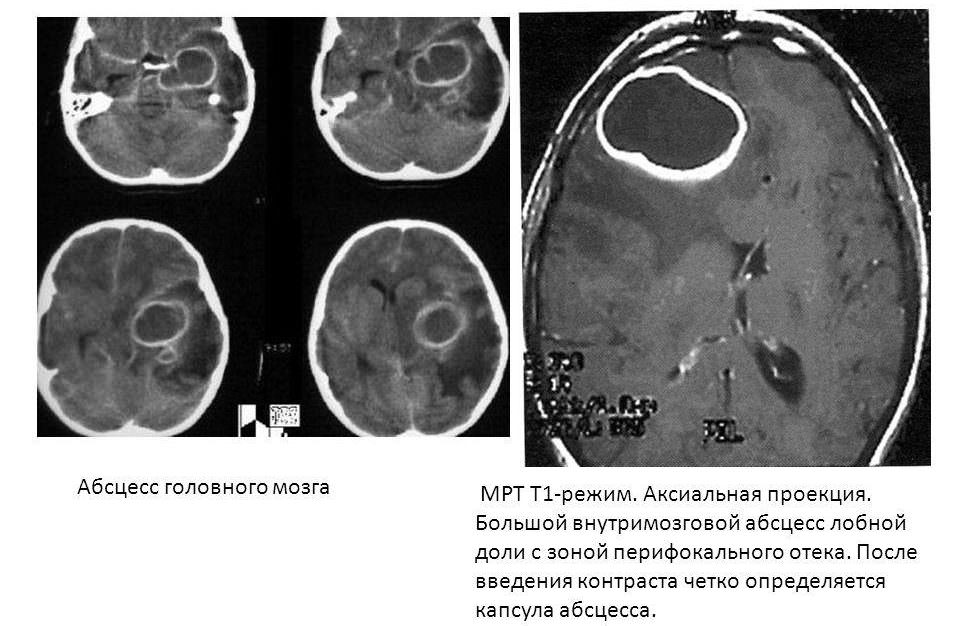

- 3 стадия (10-13 дней). Вокруг гнойной полости образуется защитная пленка, которая не дает образованию распространяться дальше.

- 4 стадия (3 неделя). Пленка полноценно уплотнилась. В некоторых случаях начинается регресс болезни или вокруг капсулы образовываются новые очаги заражения.

Её эффективность доказана в случаях, когда гнойник расположен глубоко в голове. Если неврология больного покажет наличие воздуха в абсцессе или ухудшение общего состояния пациента – новообразование нужно удалять.

Полное извлечение капсулы поможет предотвратить повторное заражение, но операцию нужно проводить осторожно, без нарушения целостности образования. Дальше антибиотики следует применять в течение 3 дней с постоянным наблюдением пациента